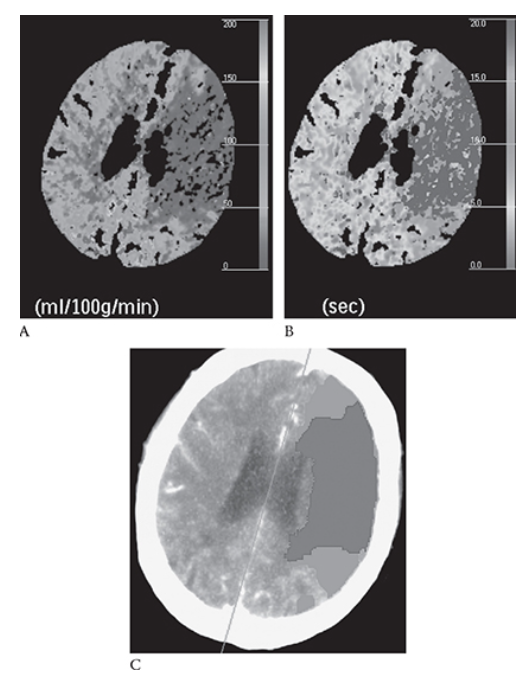

What is A

Ischemic Stroke. NECT axial image shows a hyperdense left MCA. There is decreased attenuation in the left MCA territory

What is B

Ischemic Stroke. NECT axial image in the same patient and loss of the gray with differentiation resulting in the “insular ribbon sign.”